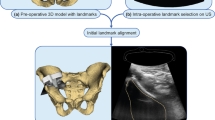

Schematic workflow of the proposed US-guided targeted biopsies of distinct CT-based radiomic tumour phenotypes. Standard-of-care contrast-enhanced (CE) CTs were used to manually segment US targetable tumour deposits in the pelvis or omentum. Automated tissue sub-segmentation was applied in selected omental lesions to remove non-tumoural fatty tissue at the segmentation edges. Spatial radiomic features were computed and the Gaussian mixture modelling clustering was applied to identify up to three habitats per tumour lesion. Habitat maps were exported and manually uploaded together with the source CT data to a US machine. Up to two biopsies per habitat were obtained and used for clinical diagnosis, as well as for research purposes

Before starting the US biopsy procedure, the CT images were registered onto the US data using a landmark-based rigid-body registration. First, the axial orientation of the CT images was registered by obtaining a US image in a strictly axial plane. Second, between one and three fusion points were used as landmarks to register the z-axis between the CT volume dataset and the US data. The first fusion point in all patients was the anterior superior margin of the pubic symphysis. The umbilicus and spina iliaca anterior superior were used as second and third fusion points. The fusion quality indicator was between 8 and 10. This can take a value between 1 and 10, where 1 indicates a poor fusion signal quality and 10 an excellent quality.

Figure 1 summarises the radiological and clinical workflow. We performed targeted CT/US fusion-guided biopsies in six patients. The demographic and clinical characteristics are shown in Table 2. Figure 2 displays the detailed imaging characteristics at each step for patient 5. For patients 2 and 5, we obtained biopsies from the pelvic lesion, and in patients 1, 3, 4, and 6, we obtained biopsies from the omental deposits. The tumour volumes of the targeted omental lesions (median = 103 cm3; range: 16–295 cm3) were smaller compared to those of the pelvic lesions (median = 520 cm3; range: 448–592 cm3). No adverse events were observed following the biopsy procedures. For patients 1 and 3, the biopsy material was insufficient for diagnosis and these patients underwent diagnostic laparoscopy that established the diagnosis of HGSOC.

Illustration of a patient with a pelvic tumour. a Routine contrast-enhanced CT images were used to manually segment the pelvic tumour (dashed line). b Spatial radiomic feature extraction and generation of habitat maps. For this patient, three tumour habitats are feasible and highlighted in blue, red, and green, respectively. c The left figure shows the US image with the co-registered CT-based tumour segmentation (dashed line). The right figure shows the CT scan overlaying the US plane, with the habitat maps highlighted in colour. The US images correspond to a different plane orientation with respect to panels a and b